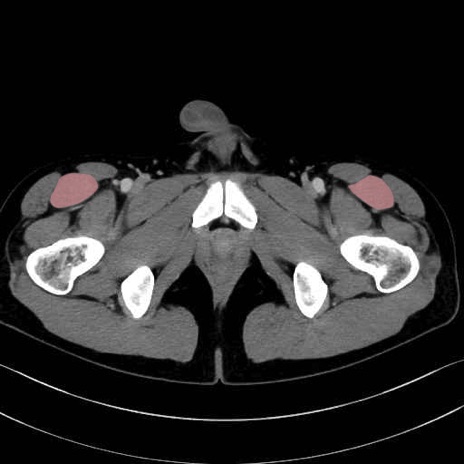

大腿筋膜張筋 (Tensor fasciae latae)

縫工筋 (Sartorius)

大腿直筋 (Rectus femoris)